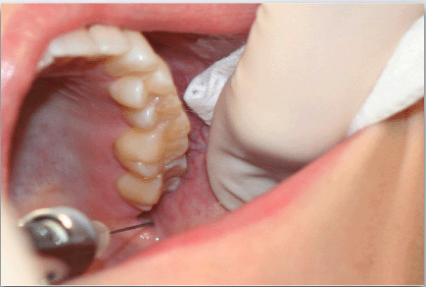

what is the proper injection site for long buccal nerve block?

buccal side of 2nd or 3rd molar (injection depth is very shallow)

what is the proper insertion point for long buccal nerve block?

Just medial to the external oblique ridge at the level of the occlusal plane

what is the proper insertion path for long buccal nerve block?

Through the mucosa and buccinator muscle until bone in gently contacted on the anterior ramus

what is the proper insertion depth for long buccal nerve block?

2 – 3 mm (very superficial)